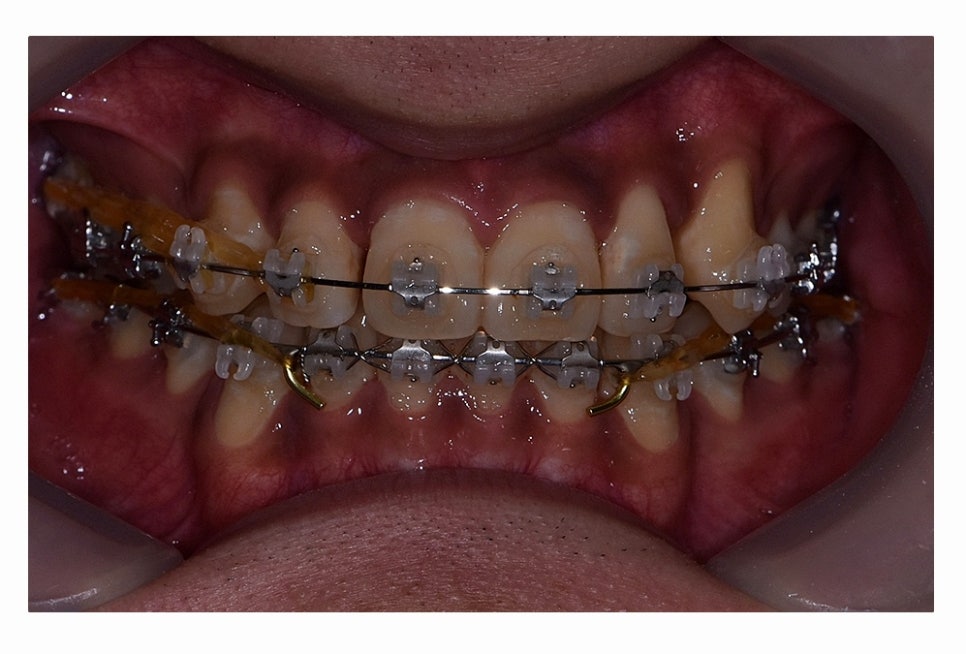

오늘 보시는 환자분의 사례처럼 덧니가 치아끼리 겹쳐 있는 경우에

치아의 이동 공간 확보를 위해서 덧니 발치 필요한 사례였으며

교합과 치아교정 후 얼굴 변화를 고려할 때도 치아교정 과정에서

발치가 필요한 사례였다고 볼 수 있어요.